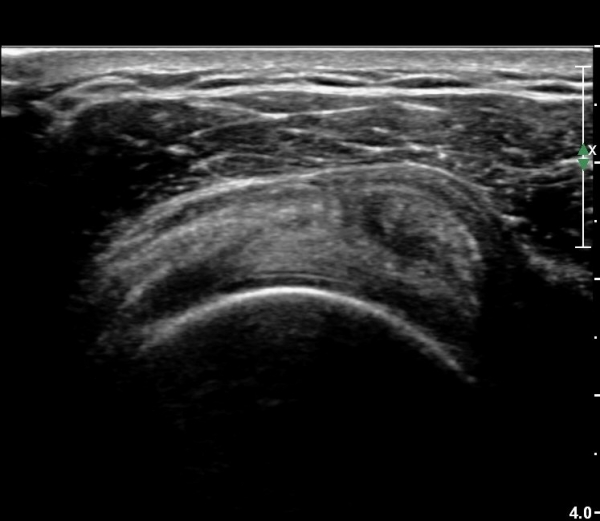

ÀÌµÎ¹Ú±Ù°Ç ÀåµÎ Ⱦ´Ü¸é°Ë»ç¿¡¼­ °ÇÁÖÀ§ ¼ö¾×Àú·ù°¡ °üÂûµÈ´Ù(»çÁø 3).

ŽÃËÀÚ¸¦ °ßºÀ ¿ÜÃø¿¡ ´ë°í ¾î±ú¸¦ ¿ÜÀüÇϸ鼭 °üÂûÇÏ´Ï ¿ÜÀü ½Ã °ßºÀ ¿ÜÃø¿¡ ¼ö¾×Àú·ù°¡

°üÂûµÇ¾î(»çÁø 10) ¿ÜÀü ½Ã °ßºÀÇÏ Ãæµ¹ÀÌ ÃßÁ¤µÈ´Ù.